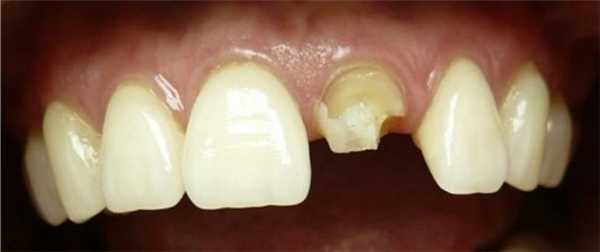

Подготовленная культя зуба к восстановлению

Культя, восстановленная по коронке